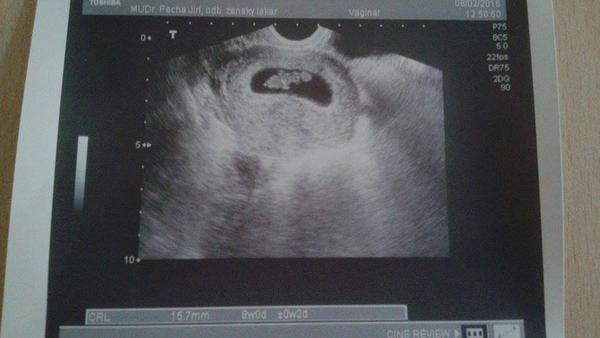

@petik607 JÉÉÉno to je úžasné....Teď jsi mě úplně rozněžnila 🙂 Nádherná fotečka 🙂 Teeda - jsem nevěděla, že už v 8.tt to jde tak krásně vidět - paráda. Jo jméno pro kluka víme - Štěpán. Můj nastávající se sice jmenuje jinak, ale na Štěpána má narozeniny..nooo a když to bude holka, tak to vůůůbec nevím..no musí to být kluk 😀 Jaké máš příznaky těhu? Je ti špatně nebo to snášíš v pohodě?

@clea89 Tak Štěpán je po Vánocích ne? 🙂 No a na holku jsme měli na výběr Terezu a nebo Emily, ale byla by to spíš ta Tereza. Jinak příznaky já neměla žádné, kdybych to neřešila, že jsem to nedostala, tak ani nevím, že jsem těhotná :D Akorát teď mi dělá v břiše divočinu :D takže teď už o něm opravdu vím.. Žádné zvracení, akorát mě v prvním trimestru hodně bolela hlava, to bylo jediné 🙂 Takže je na mě vidět, že jsem hodně přibrala, mám nahoře skoro 14kg a to jsem v 25tt 🙂 Jinak ti pošlu fotku, jak vypadá první ultrazvuk při 6+5tt 🙂 Jinak ti přeju hodně štěstí, aby se vám to povedlo 🙂